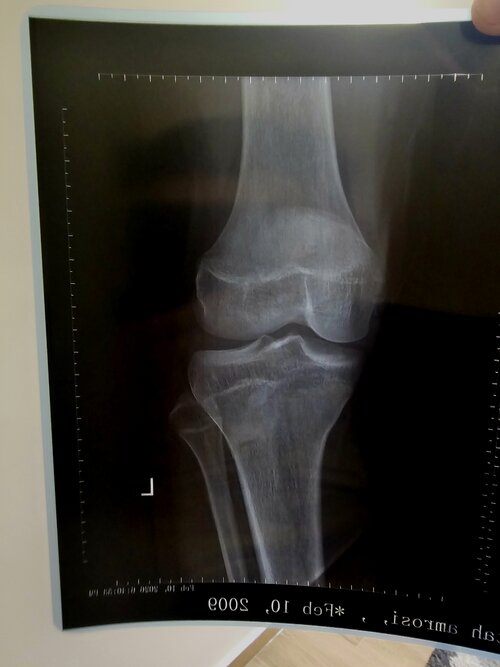

this js my knee and wrist can you tell me how i it seems i have left? would gh be worth it. il alr on ai

Your proximal tibia is starting to fuse, femur is in partial fusion but still has growth potential aswell as your fibula. I cant tell how much growth is left because it depends on your recent growth velocity so you can go from there. Did u grow recently?

arkund 2-3 cm in the past year but ive been undereating badly my whole life. i might start gh soon ill consult an endocrine doctor to prescribe it. but im guessing if i start gh and start eating well again could i have some proper gains? also ty for helping me out

Doctors wont prescribe it to older people they only do to deficient ppl, if u do gh i would also do ai and if u cant get it try being in a caloric surplus

it might not be effective for you if your estrogen has peaked in the pas but you could still try,you'll also need like 0.4iu of hgh per kilogram of bodyweight along with it